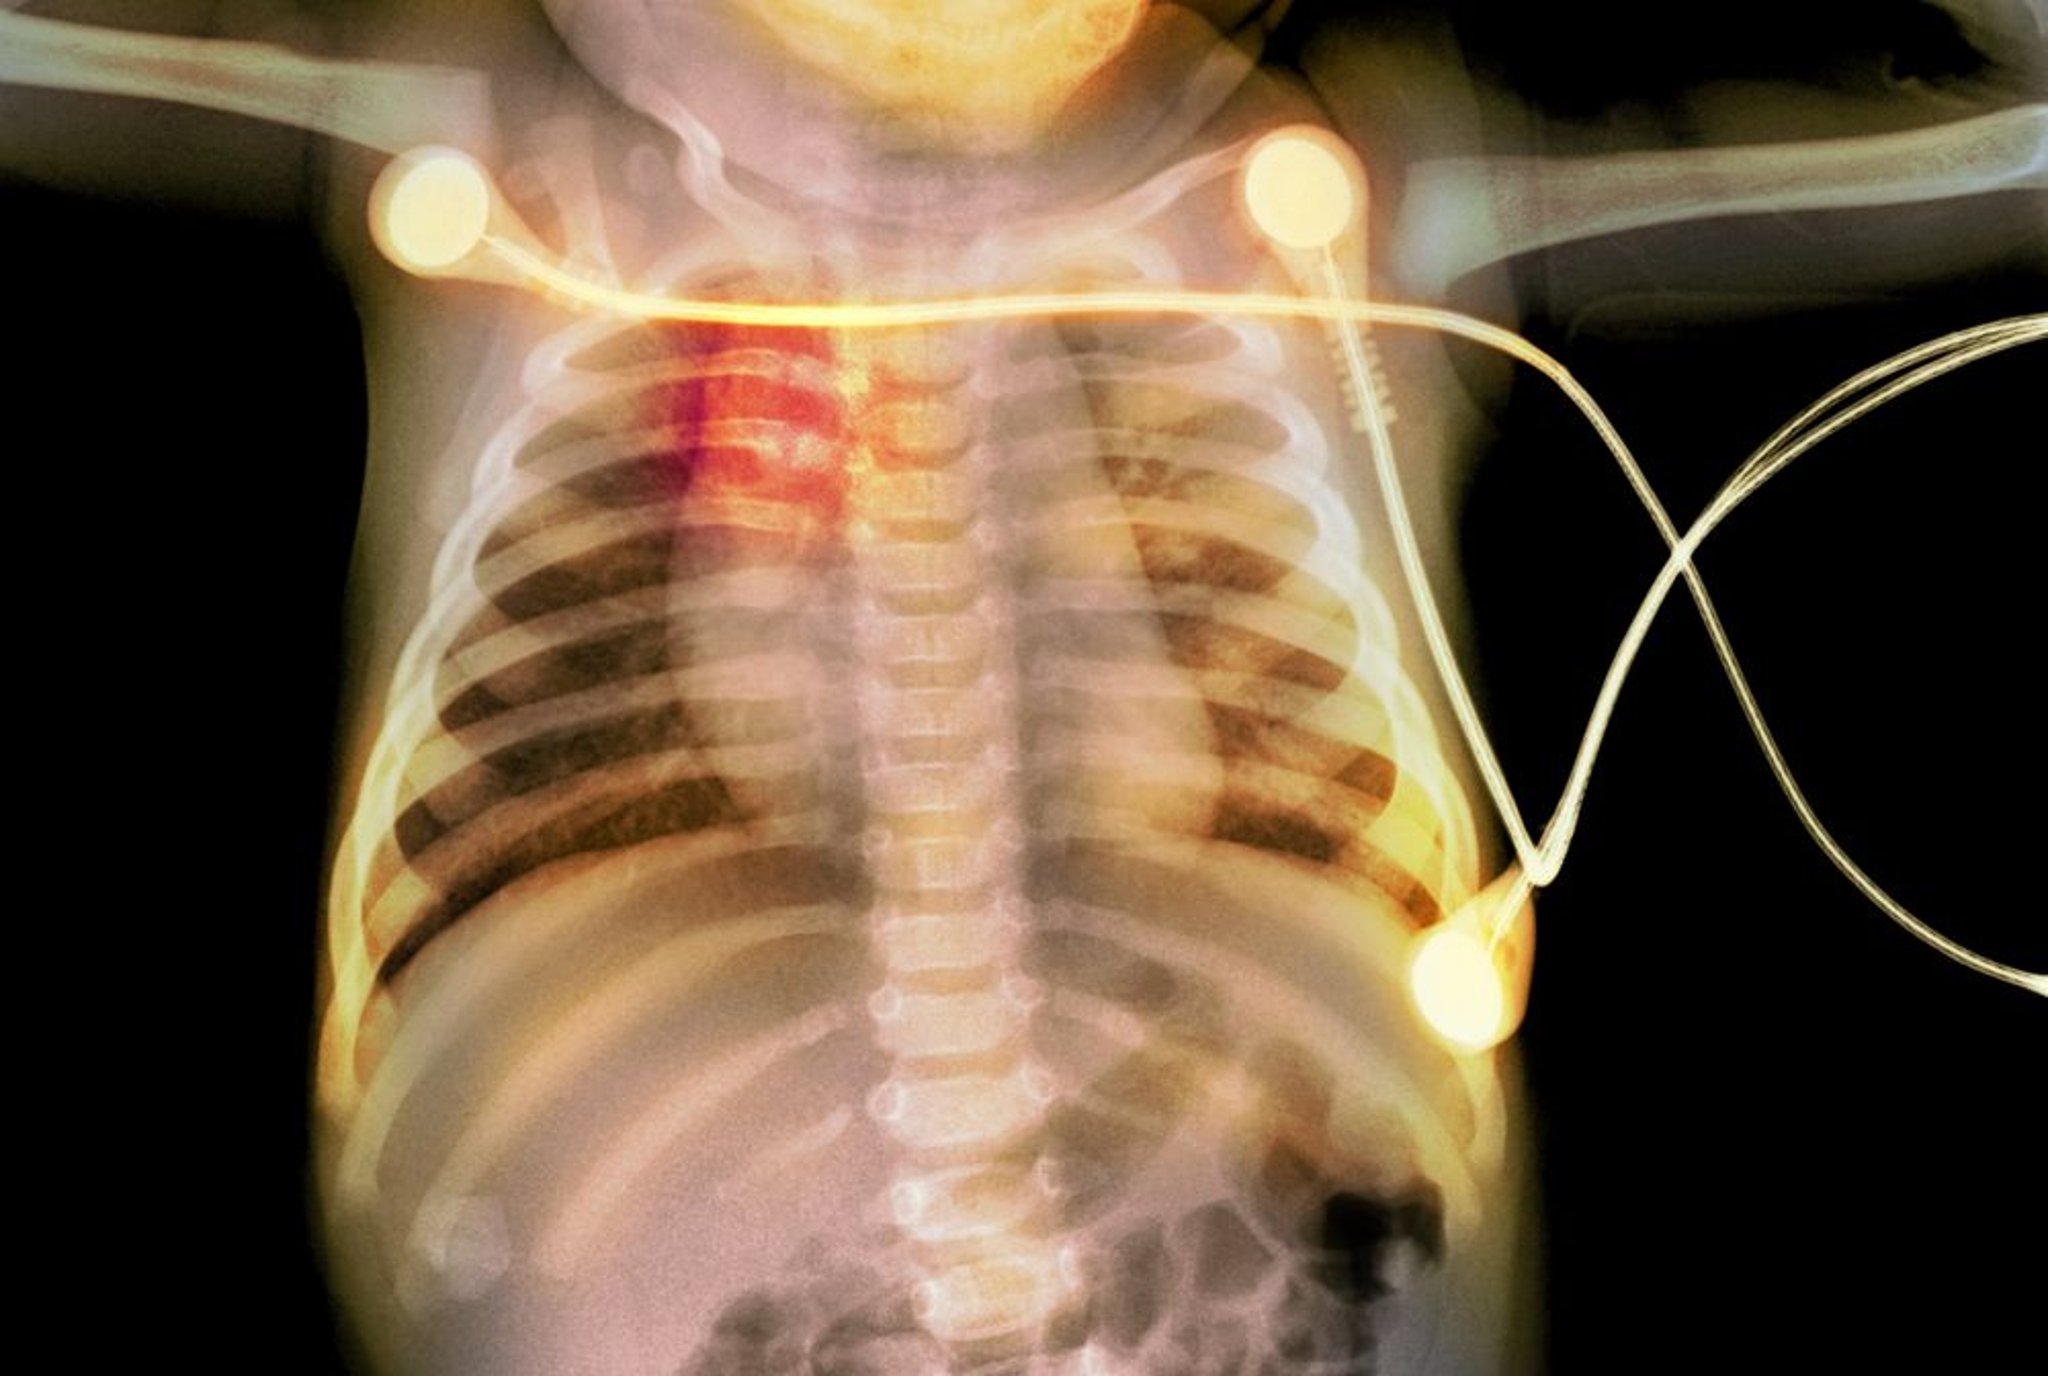

Fracturas costales en un lactante

Esta radiografía muestra fracturas costales (resaltadas en rojo) en un lactante, lo que sugiere maltrato infantil.